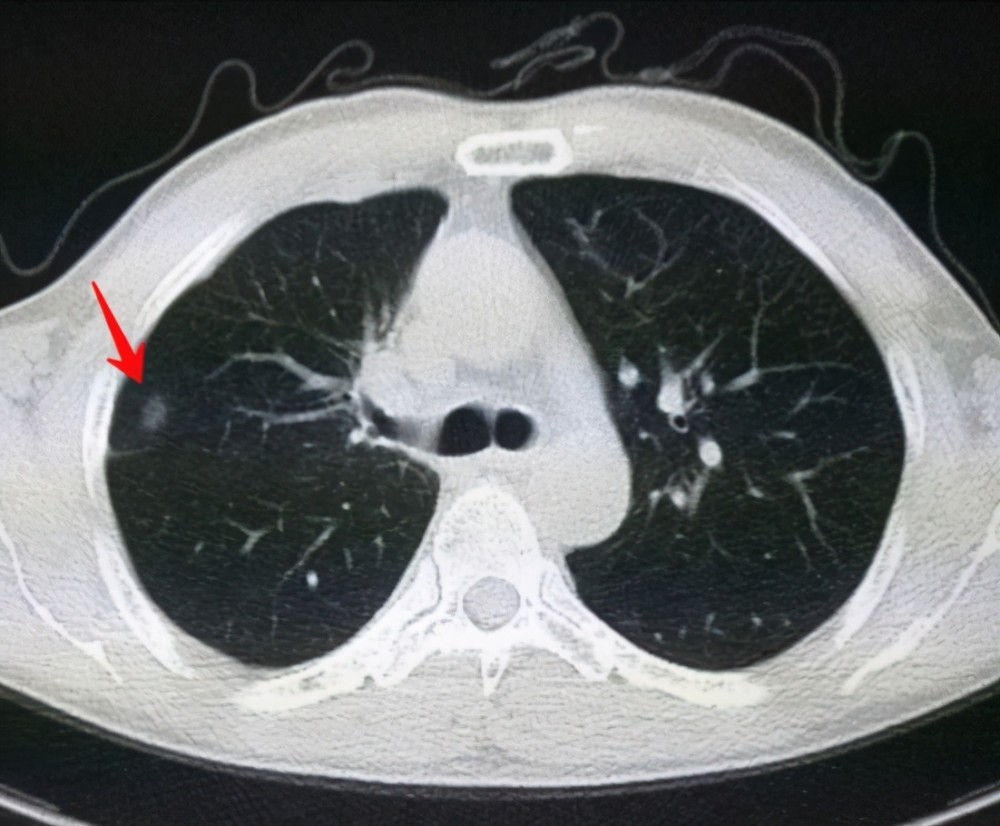

6、定期體檢:定期進(jìn)行肺部檢查,及時發(fā)現(xiàn)并治療肺結(jié)節(jié)。

對于已經(jīng)發(fā)現(xiàn)肺結(jié)節(jié)的患者,應(yīng)及時就醫(yī),進(jìn)行進(jìn)一步的檢查和治療,醫(yī)生會根據(jù)患者的具體情況制定個性化的治療方案,包括藥物治療、手術(shù)治療等,早期發(fā)現(xiàn)、早期治療是提高肺結(jié)節(jié)治愈率的關(guān)鍵。